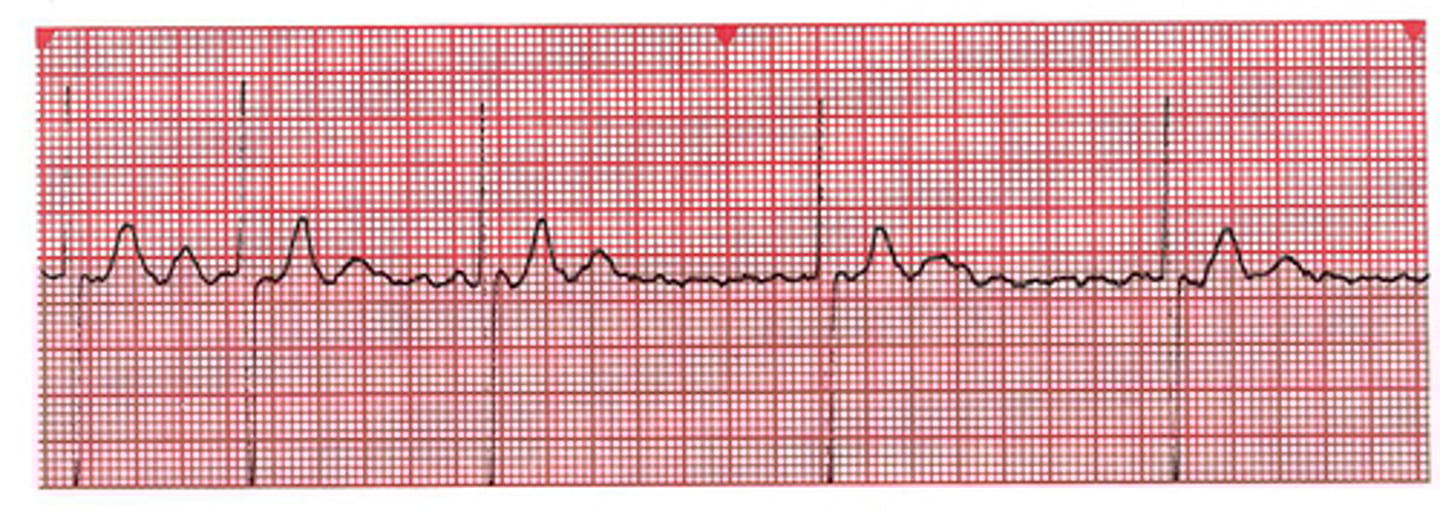

NSR

Which Arrythmia is this?